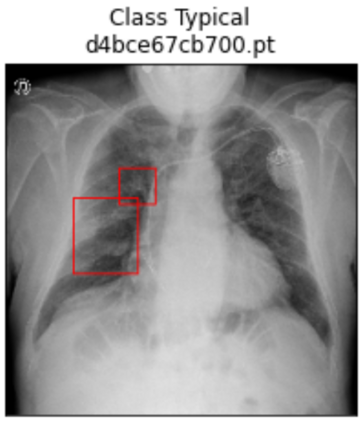

Deep learning technologies have already demonstrated a high potential to build diagnosis support systems from medical imaging data, such as Chest X-Ray images. However, the shortage of labeled data in the medical field represents one key obstacle to narrow down the performance gap with respect to applications in other image domains. In this work, we investigate the benefits of a curricular Self-Supervised Learning (SSL) pretraining scheme with respect to fully-supervised training regimes for pneumonia recognition on Chest X-Ray images of Covid-19 patients. We show that curricular SSL pretraining, which leverages unlabeled data, outperforms models trained from scratch, or pretrained on ImageNet, indicating the potential of performance gains by SSL pretraining on massive unlabeled datasets. Finally, we demonstrate that top-performing SSLpretrained models show a higher degree of attention in the lung regions, embodying models that may be more robust to possible external confounding factors in the training datasets, identified by previous works.